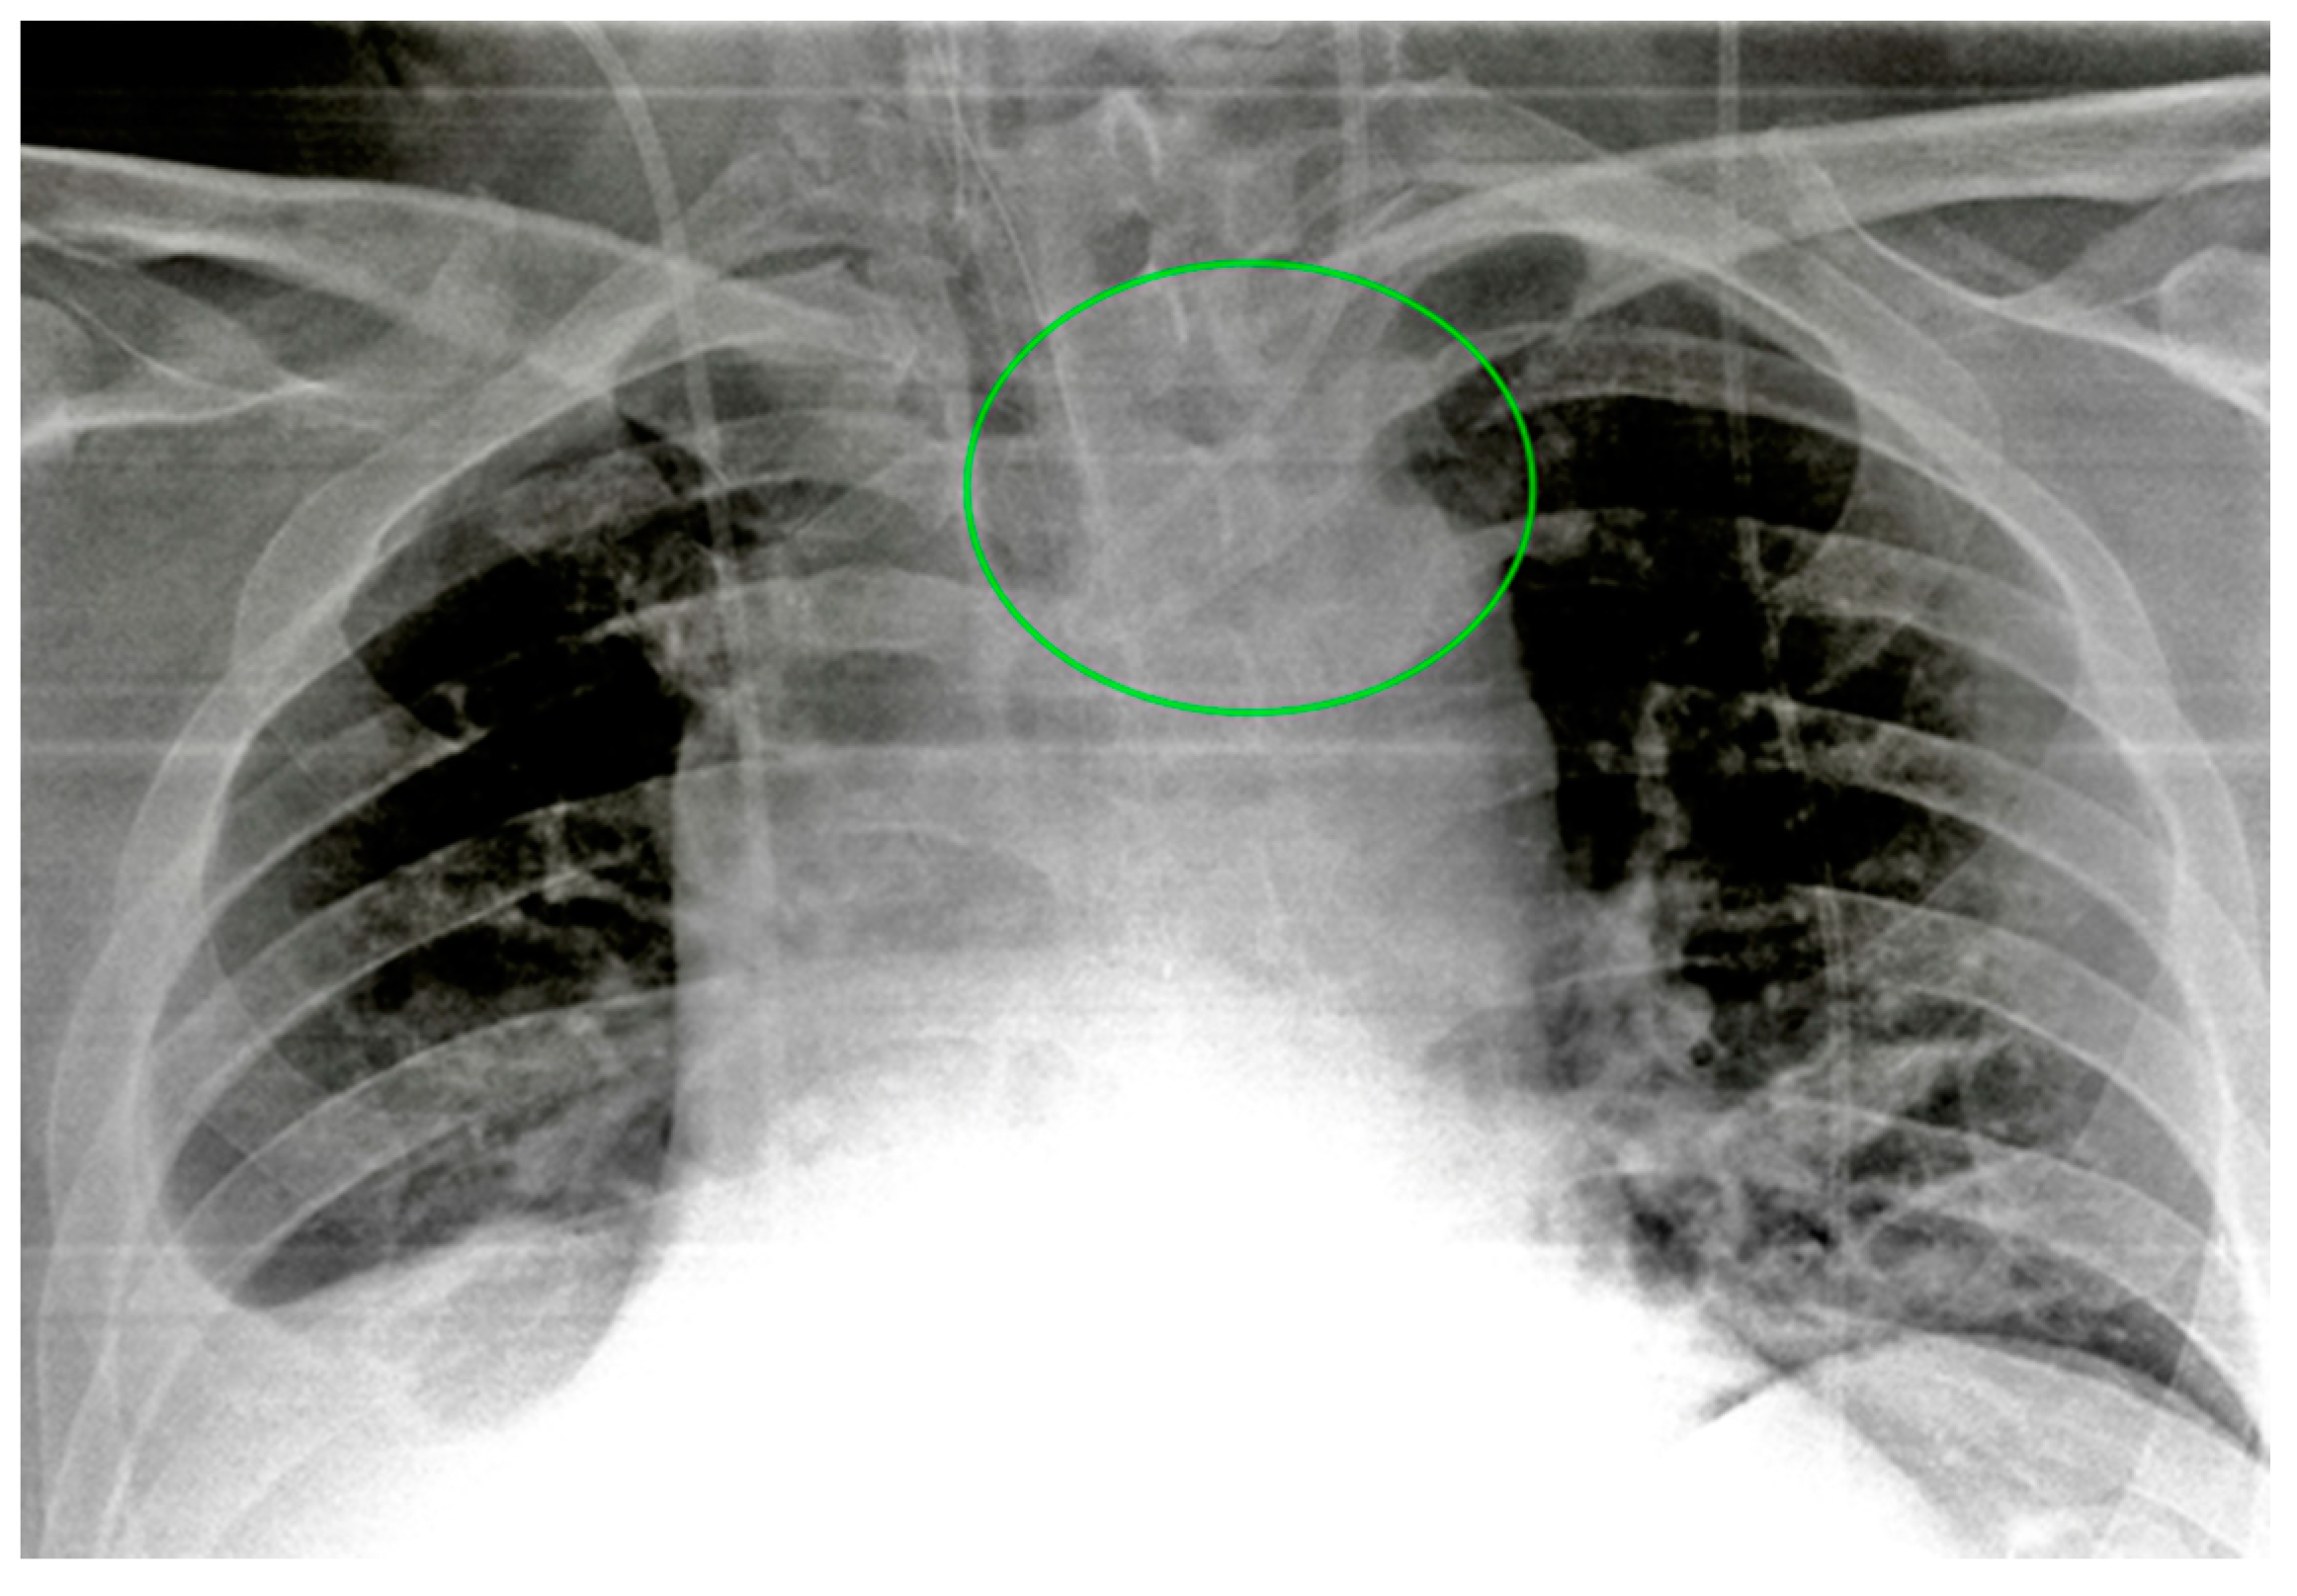

Figure 5.

A detail of a CXR showing a left jugular CVC looping with tip ending in the left jugular vein (green circle). Note that due to the underexposure of the CXR, the device is difficult to detect.